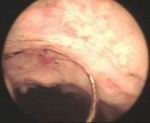

Prostatic enlargement is a comman problem is old age. By TURP nearly all patient who requires surgery for prostate can be treated successfully without any incision. Under anesthesia per urethral scope is inserted & under vision prostate is resected. Patient requires 2 to 4 days hospitalization & 1 week rest. Usually patient does not requires blood transfusion & patient can tolerate endoscopic surgery very well without risk of incontinance of urine.